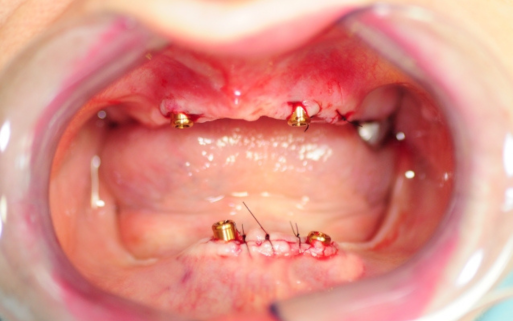

Szczególnie polecamy metodę All-on-4™, która zapewnia nowe, trwałe zęby, mocowane na czterech implantach – bez potrzeby przeszczepu kości. To idealna opcja nawet dla pacjentów z zanikiem kości, gwarantująca komfort i funkcjonalność na lata.

Oferujemy nowoczesne rozwiązanie, jakim jest proteza mocowana na 2 implantach. Implanty są wszczepiane w miejscach brakujących zębów, a następnie łączone za pomocą specjalnych łączników lub belki z protezą. Dzięki temu proteza jest stabilna i pewnie trzyma się w ustach, umożliwiając swobodne jedzenie, mówienie oraz uśmiechanie się.

Przed i Po Naszych Klientów

Zajmuję się zarówno wszczepianiem implantów, jak i rekonstrukcją ubytków kostnych, a także podnoszeniem dna zatoki szczękowej, co pozwala na uzyskanie optymalnych warunków do wszczepienia implantów, nawet w przypadku dużych ubytków kostnych.